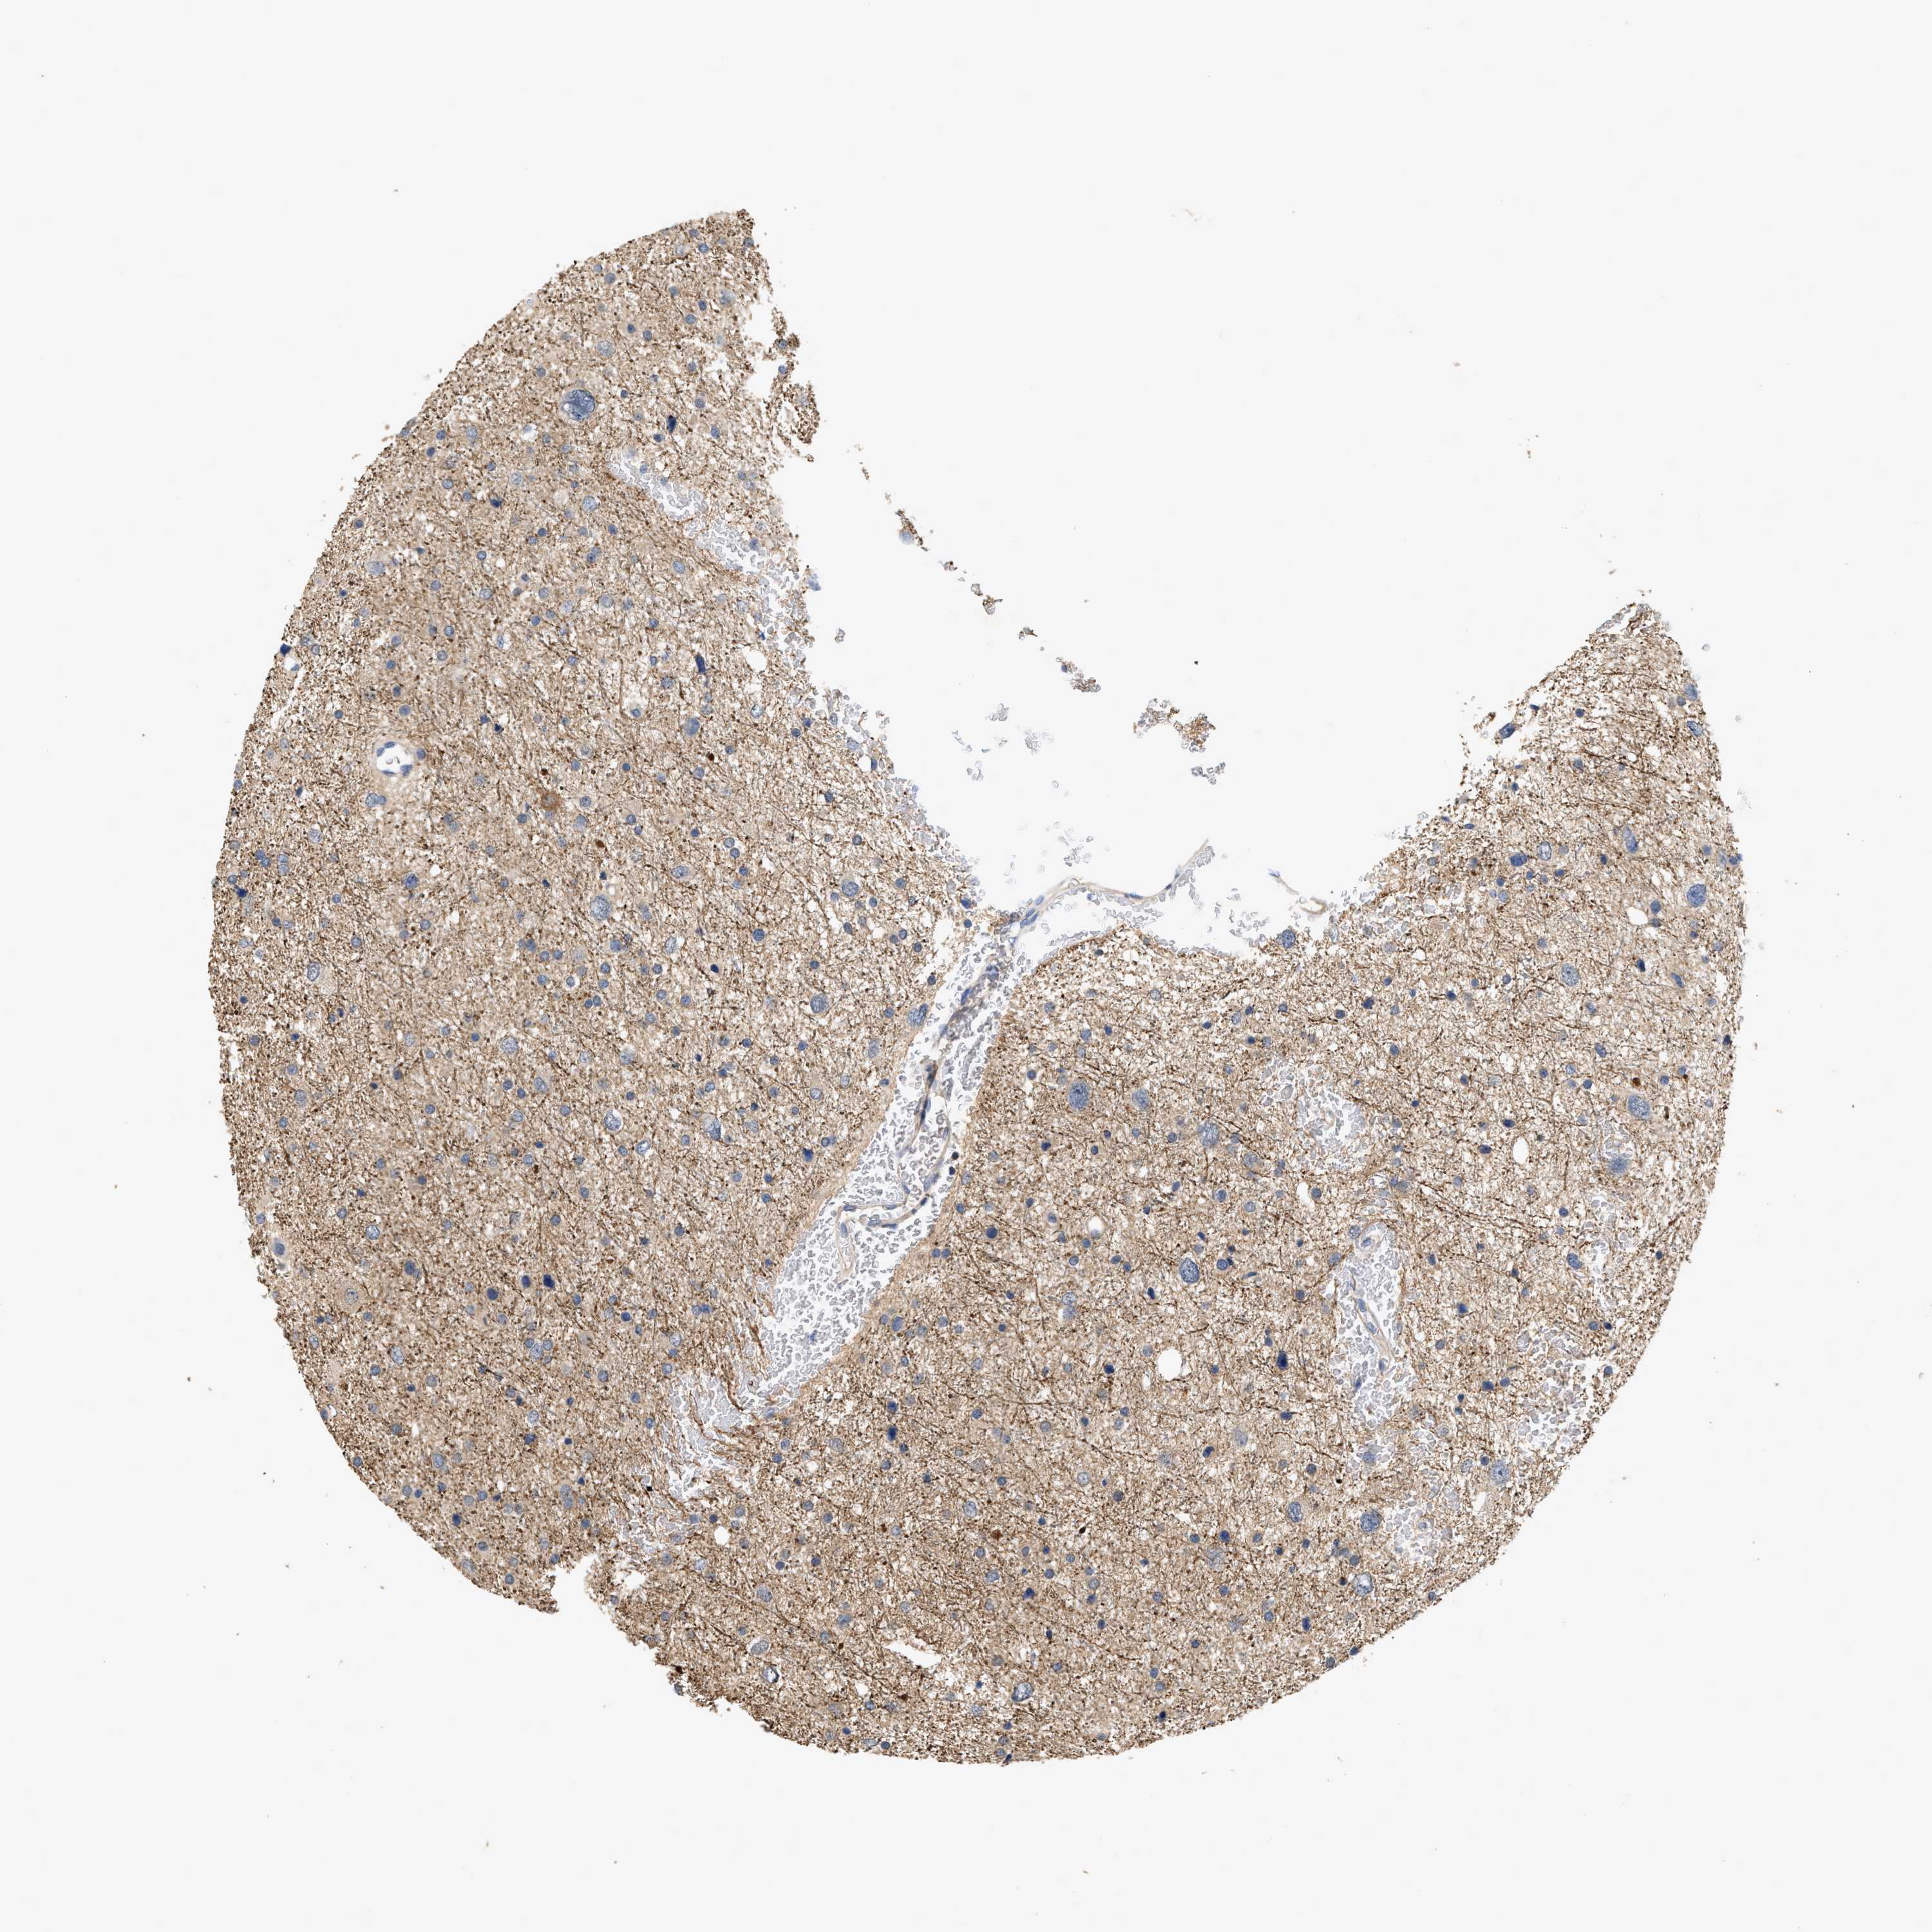

GLIOMA - Protein expressioni

A mouse-over function shows sample information and annotation data. Click on an image to view it in a full screen mode. Samples can be filtered based on level of antibody staining by selecting one or several of the following categories: high, medium, low and not detected. The assay and annotation is described here.

Note that samples used for immunohistochemistry by the Human Protein Atlas do not correspond to samples in the TCGA dataset.

Antibody stainingi

Antibody staining in the annotated cell types in the current human tissue is reported as not detected, low, medium, or high, based on conventional immunohistochemistry profiling in selected tissues. This score is based on the combination of the staining intensity and fraction of stained cells.

Each image is clickable and will lead to virtual microscopy that enables deeper exploration of all samples and also displays staining intensity scores, fraction scores and subcellular localization as well as patient and tissue information for each sample.

Antibody HPA019086

Antibody HPA030619

Staining

High

Medium

Low

Not detected

Intensity

Strong

Moderate

Weak

Negative

Quantity

>75%

75%-25%

<25%

None

Location

Nuclear

Cytoplasmic/membranous

Cytoplasmic/membranous,nuclear

Glioma, malignant, High grade

Glioma, malignant, Low grade